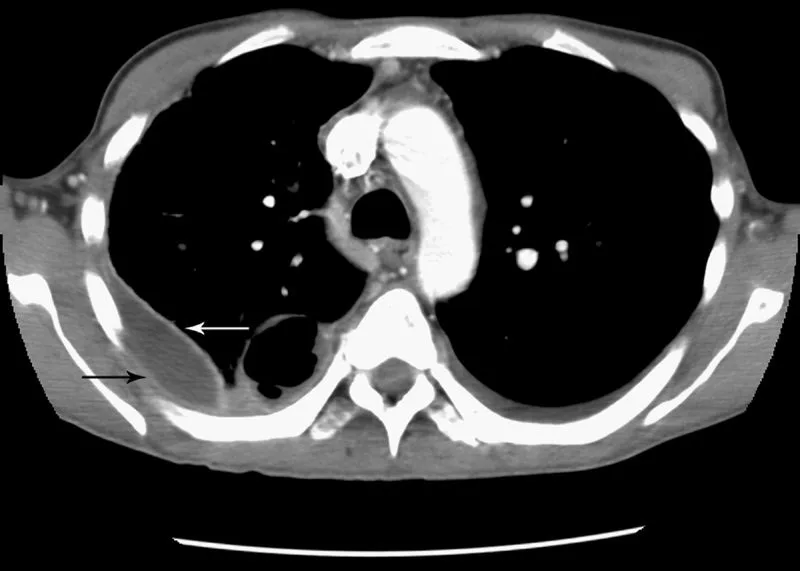

- Chest CT with contrast: Best test to confirm empyema, identify loculations, and guide drainage. May show the "split pleura" sign.